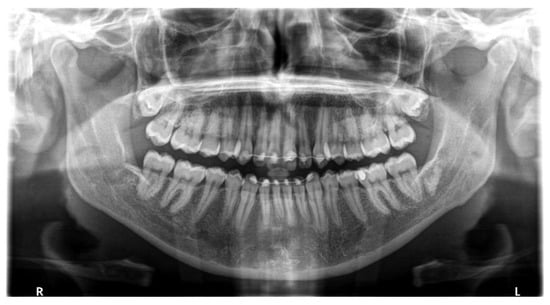

2. Materials and Methods

2.7. Radiographic Evaluation